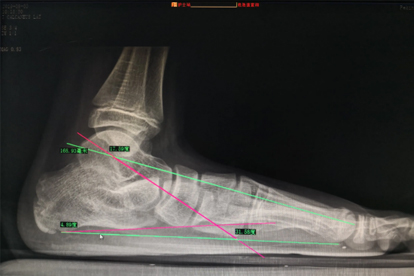

少数患者可能因术前畸形严重、肌力失衡未纠正或康复不彻底,遗留轻微步态异常。术后足弓高度可能仍低于正常水平,长时间行走后偶发酸胀感。若合并神经肌肉疾病或关节退变,功能恢复可能受限。术后3-6个月是功能恢复关键期,需定期复查评估跟骨排列和肌腱愈合情况。